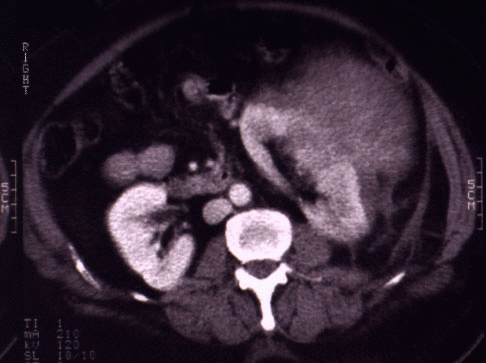

Fig. 1: Tomografía axial computerizada espiral con contraste intravenoso. Se observa un riñón izquierdo aumentado de tamaño, con retraso del nefrograma y área heterogénea en su cara lateral donde no se identifica parte del borde renal. El riñón se encuentra desplazado medialmente por una masa densa, confinada por la fascia renal que se corresponde con un hematoma subcapsular y perirrenal. |